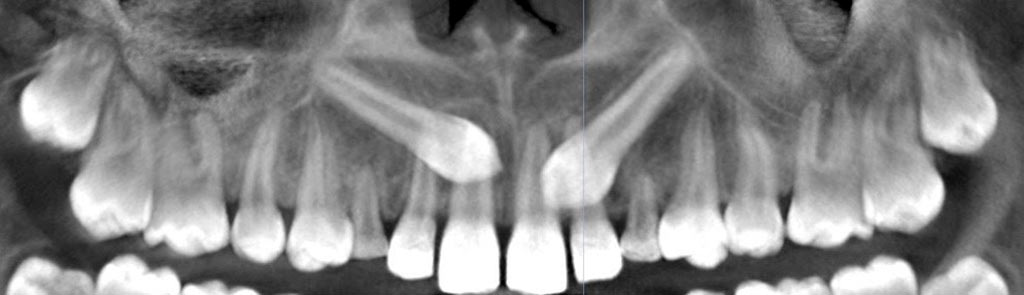

Tracción de canino con k9